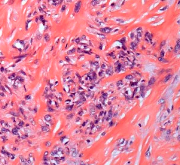

纤维肉瘤

应用机器人导航结合 3D 打印个性化假体治疗小腿黏液纤维肉瘤一例